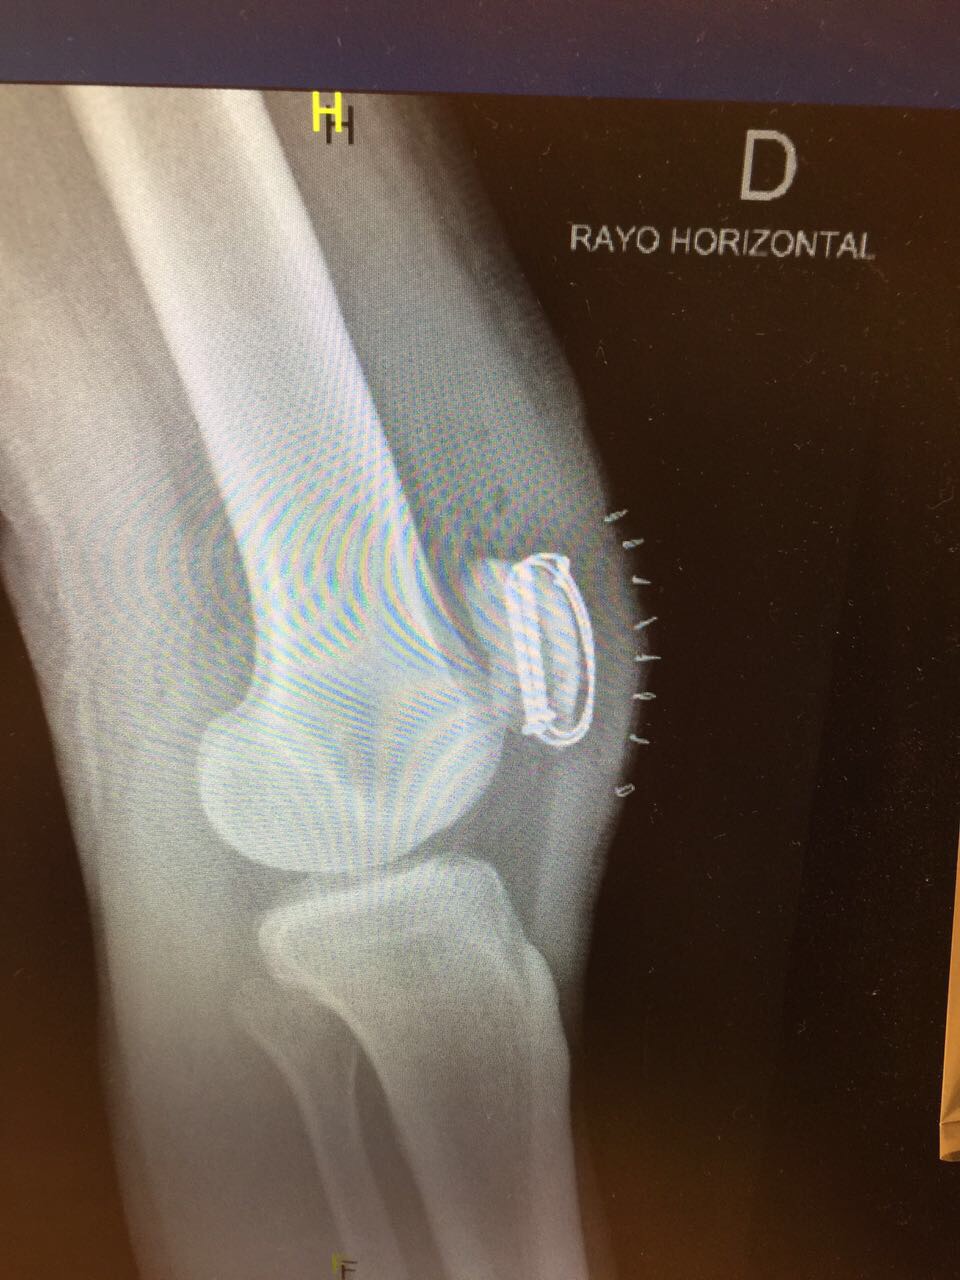

Under gårdagen var jag även på kontrollröntgen och konstaterade att allt såg bra ut och att skruvarna och ståltrådarna placerats som de skulle 🙂